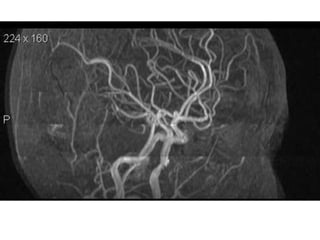

NORMAL MRA

Arteries of the brain (cranial view) - MRA

1. Anterior cerebral artery

2. Anterior communicating artery

3. Basilar artery

4. branches (in insula) of middle

cerebral artery

5. Cavernous portion of internal carotid

artery

6. Cervical portion of internal carotid

7. Genu of middle cerebral artery

8. Intracranial (supraclinoid) internal

carotid artery

9. Middle cerebral artery

10. Ophthalmic artery

11. Petrous portion of internal carotid

12. Posterior cerebral artery

13. Posterior cerebral artery in ambient

cistern

14. posterior cerebral artery in

interpeduncular cistern

15. Posterior communicating artery

16. Posterior inf cerebellar artery.

17. Quadrigeminal portion of posterior

18. Superior cerebellar artery

19. Vertebral artery